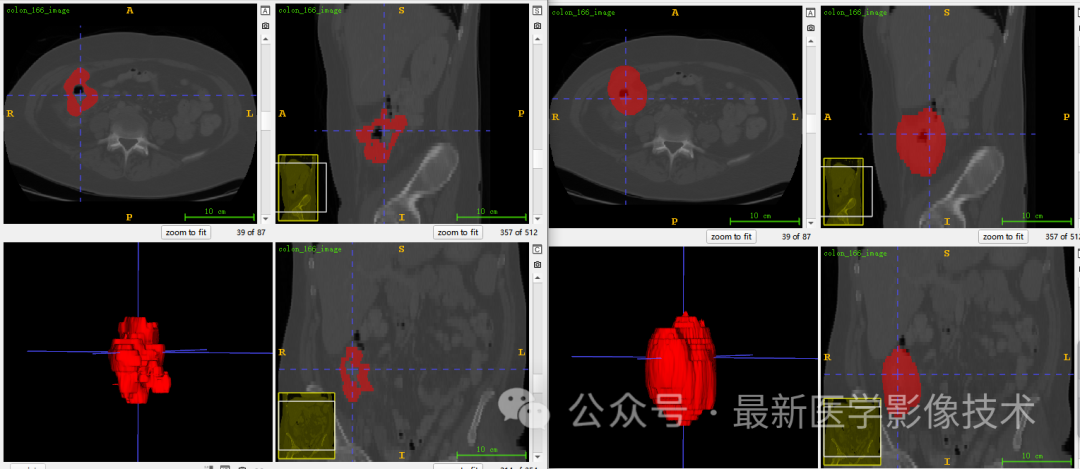

5、验证集分割结果

左图是金标准结果,右图是预测结果。